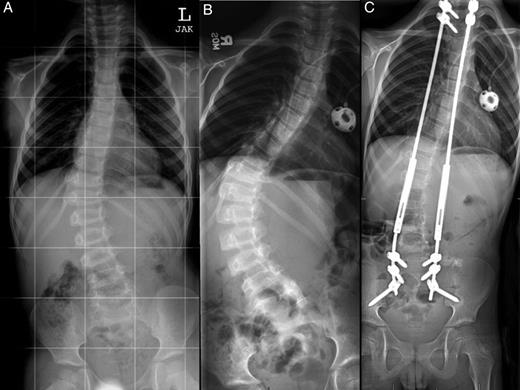

One month after completing radiation (3 years since diagnosis), he reported increasing back pain along with failure to thrive and resultant difficulty attending school. Plain films demonstrated continued relative stability of his curvature at 44 degrees, and his increased back pain was attributed to early toxicity from radiation. Over the following 2 months, his back pain continued to progress, he also complained of neck pain and his mom noted subjective worsening of his curve. His narcotic requirement had increased, and imaging confirmed worsening of his thoracolumbar scoliosis with his curve measuring 64 degrees (Figs 2B and 3A). At this point, we recommended surgical intervention with placement of dual growth rods given the significant curve progression and deterioration in functional status (McCormick Grade III).

Anterior-posterior (AP) plain films of the spine at the time of diagnosis (A), after curve progression (B) and 1 year after growing rod insertion (C). Measured Cobb angles were 32 degrees (A), 64 degrees (B) and 22 degrees (C), respectively.

We placed dual growth rods from T2 to the ilium with a posterior spinal fusion from T2 to T3 and L5 to the ilium. The surgical technique has been previously described in detail by Akbarnia et al. [7]. Motor evoked potentials and somatosensory evoked potentials remained stable throughout the entirety of the case. Postoperatively, he had full strength.

He had three total lengthening procedures in the first 14 months since placement of the growing rods with improvement in his scoliotic curvature to 22 degrees (Figs 2C and 3B). Eighteen months after insertion of his growing rod construct, he developed hardware infection requiring hardware removal. He is scheduled to undergo definitive fusion in the near future. He has returned to his initial independent functional status with minimal gait abnormality (McCormick Grade II) and is able to participate in activities such as biking and skateboarding. He is now 10 years old.